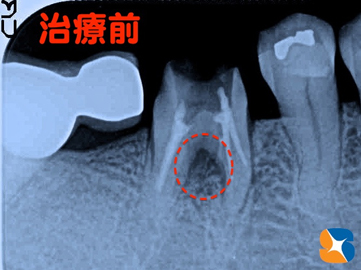

歯茎が膿んでいた所をレントゲンで確認

コラム「歯茎が膿んでいた所をレントゲンで確認」の画像